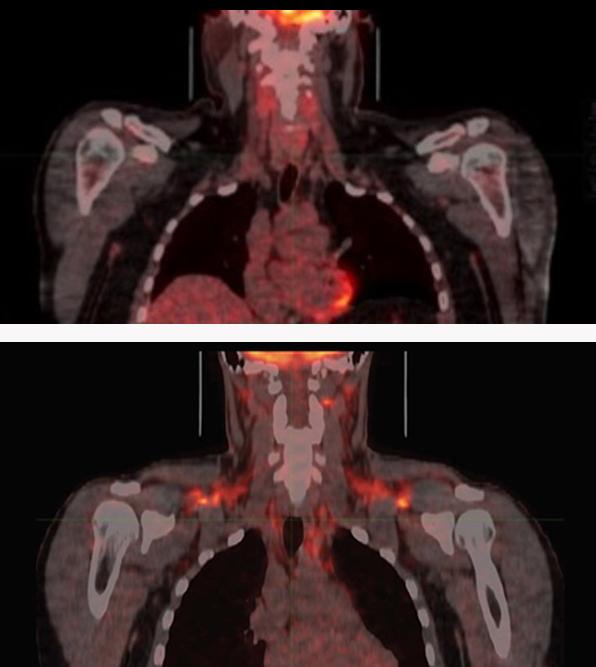

Brown fat breaks down blood sugar (glucose) and fat molecules to create heat and help maintain body temperature. Cold temperatures activate brown fat, which leads to various metabolic changes in the body. Most of our fat, however, is white fat, which stores extra energy. Too much white fat builds up in obesity. Researchers have been working to harness brown fat’s activity in order to treat obesity, diabetes, and other metabolic disorders.

Based on measurements taken at normal room temperature, the team classified 17 of the men as having high brown fat activity and 16 as low activity. They then exposed the men to a temperature cold enough to activate their brown fat (but not low enough to cause them to shiver) for two hours.